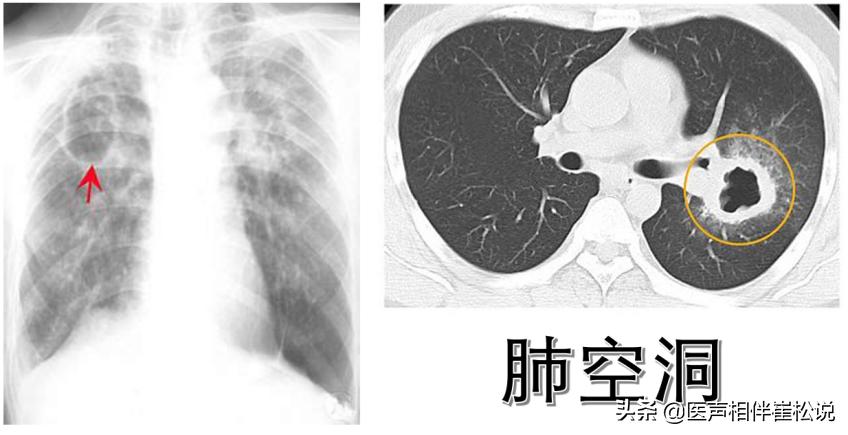

但是有些人的肺里面可能会有空洞,这个空洞里面含有大量的结核杆菌,然后这个空洞正好通着我们的气管,于是结核杆菌就会通过气管排出。

综合以上所有的症状,咳嗽、咳痰、痰里带血丝、低热、消瘦,那就很有可能得了肺结核。这时候赶紧去医院拍片检查,片子上一看就能知道你是几型的肺结核。一旦确诊了肺结核,下一步就是我们上面提到的痰里面找结核杆菌的化验,看是否有传染性。有传染性就隔离,这样才能保证不会传染给自己的家人。